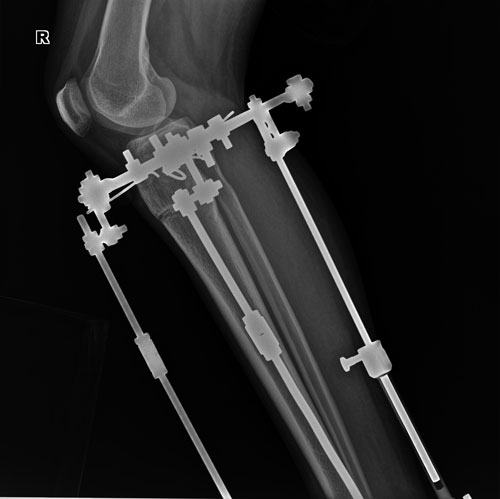

рентген в 60 дней.

Вложения

IM-0001-0001-0001(1).jpg

IM-0001-0001-0002(1).jpg

IM-0001-0001-0002.jpg